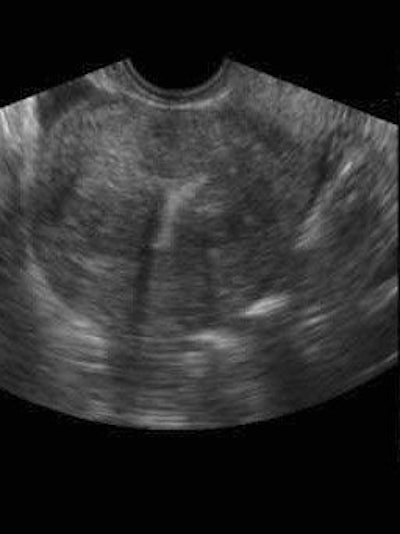

![]() |

| Three-dimensional ultrasound images showing septate uteri. Images courtesy of Dr. Beryl Benacerraf. |

Foremost among these is the coronal view of the uterus, an only-in-3D image that can much more definitively distinguish the bicornuate from the septate from the unicornuate uterus.

"These kinds of images are incredibly important, particularly for the infertility patient," said Benacerraf, noting that women with septate uteri are at much higher risk for miscarriage, preterm labor, and other adverse effects.

With 3D, the sonographer can also measure the width and the depth of the septum, Benacerraf said, "which will be a very good guide for the surgeon who is going to be resecting the septum."